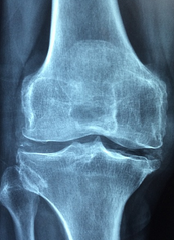

1. 관절 통증 완화

MSM은 관절의 주요 구성 성분으로, 관절의 유연성을 증진시키고 연골 기능을 유지합니다. 또한, 강력한 항염증 효과를 통해 관절 통증과 부기를 완화하는 데 도움을 줍니다. 한 연구에서는 45~90세의 관절염 환자들이 12주간 MSM을 섭취한 결과 관절 통증, 뻣뻣함, 부기, 관절 기능의 불편함이 줄어들면서 삶의 질이 개선되는 것으로 나타났습니다.

2. 관절염 증상 개선

관절염은 염증성 질환으로, 주요 증상은 관절의 통증, 뻣뻣함, 관절 기능 범위의 제한입니다. MSM은 이런 관절염 증상을 개선하기 위한 대체 요법으로 사용되곤 하는데, 이는 MSM의 강력한 소염작용 때문입니다. 일례로, 한 연구에서는 무릎 관절염이 있는 환자 49명을 대상으로 12주간 MSM을 섭취하게 했습니다. 그 결과 MSM을 섭취한 환자들의 무릎 통증과 경직이 감소하고 신체 기능이 개선되었습니다.